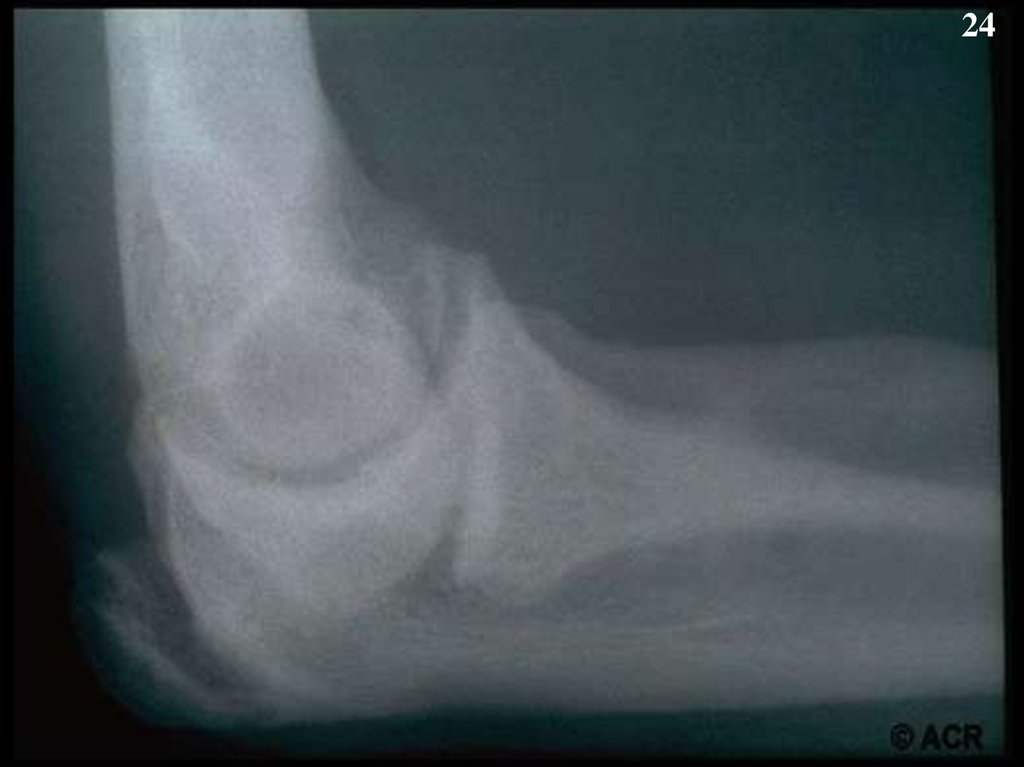

24.

24